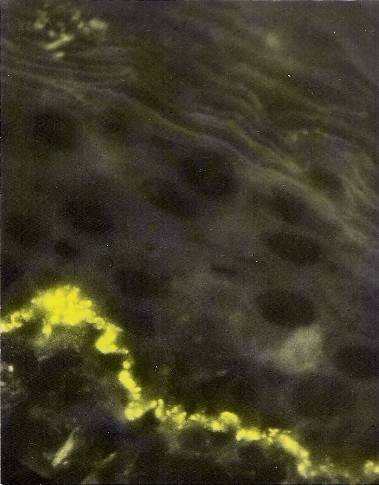

- Именно, Кошевенко Ю. Н. в 1972 году первым в отечественной дерматологии поставил реакции тканевой иммунофлюоресценции РИФ Coons (и прямую, и непрямую), более того получил препараты самые лучшие из существовавших! Вот они:

Таких качественных и показательных микропрепаратов при красной волчанке не получал больше никто — ни в СССР, ни за рубежом. Почему? Да потому, что Ю. Н. делал в микротоме-криостате срезы тканей толщиной всего 4 микрона (тогда как все остальные — 10-15 микрон). Делал с помощью надеваемого на нож своего «Приспособления для снятия срезов», оформленного как рац.предложение № 14.